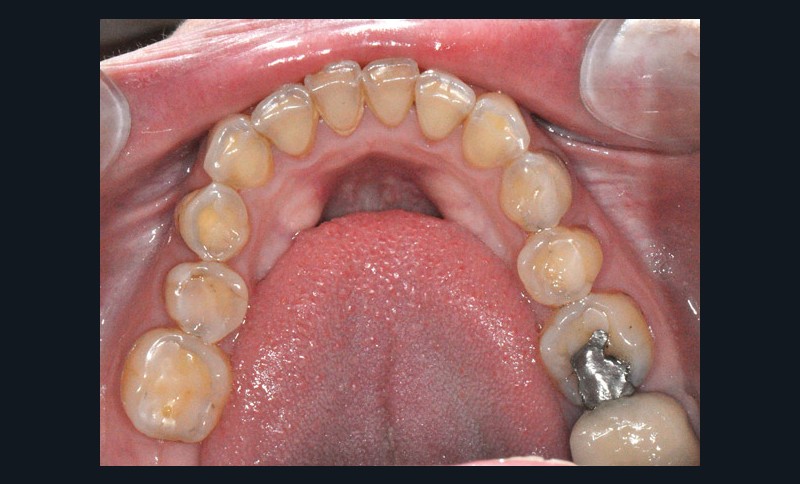

À l’examen clinique (fig. 2 à 4), on observe :

– l’absence de 17, 27 et 47 (suite de lésions carieuses volumineuses) ;

– un parodonte sain ;

– des érosions sévères généralisées, symétriques et bilatérales (occlusales, palatines et vestibulaires au maxillaire) ;

– des lésions carieuses débutantes de site 3 ;

– des obturations préexistantes infiltrées ;

– une vitalité pulpaire conservée sauf au niveau des prémolaires maxillaires ;

– une usure des bords libres des incisives mandibulaires